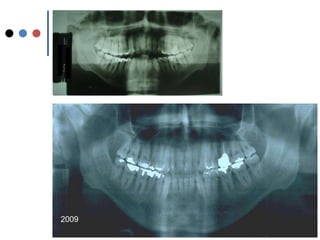

O documento apresenta registros odontológicos de um paciente ao longo de vários anos, incluindo panorâmicas iniciais e subsequentes, remodelações de arcadas dentárias superiores e inferiores ao longo de 7 meses, vedamentos labiais e registros de máxima intercuspidação e guias caninas nas datas listadas.